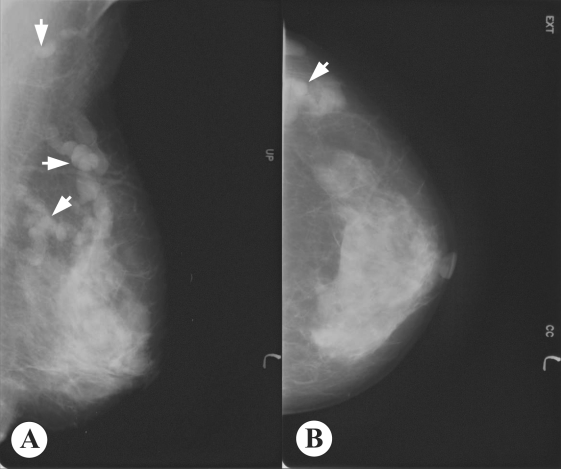

Mammography showed multiple, well-defined, isodense, lobular, and continuous cord-like structures in the upper outer quadrant of the left breast (Fig. 1). Ultrasonographic findings also showed well-defined, hypoechoic, tubular masses with folded band-like tracts and a tubule-in-tubule appearance, in the parenchymal layer of the left breast (Fig. 2). A neoplastic disease could not be ruled out, and therefore, fine needle aspiration biopsy was performed on the breast mass, which showed no evidence of neoplastic diseases. Then, breast sparganosis was suspected.

Ultrasonographic findings may also be useful for the pre-operative diagnosis of breast or other organ sparganosis (Chung et al, 1995; Cho et al., 2000; Kim et al., 2005). In breast sparganosis, elongated, folded, band- or tunnel-like hypoechoic tubular structures in heterogenous, hyperechoic masses are characteristic (Chung et al., 1995), whereas in subcutaneous and musculoskeletal sparganosis, serpiginous, cystic, tubular tracts, with internal anechogenicity and posterior echo enhancement, are important characteristics (Cho et al., 2000). Intraluminal lesions formed by the larvae or debris and peritubular echo changes produced by chronic inflammatory reactions have been noted in a half of musculoskeletal sparganosis cases (Cho et al., 2000). However, findings of elongated, serpiginous, and tubular structures may also be obtained in other types of diseases, such as, ectatic ducts, radiation edema, superficial thrombophlebitis, and congestive heart failure (Chung et al, 1995; Kim et al., 2005). Nevertheless, such findings together with high antibody titers against sparganum, and characteristic mammography and ultrasonography findings will be very useful for a pre-operative diagnosis of sparganosis.

Fig. 2

Ultrasonograms of the present sparganosis case, showing a well-defined hypoechoic, tubular mass with internal heterogeneous echogenicity, and tubule-in-tubule appearance in the subcutaneous layer of the upper outer quadrant of the left breast.